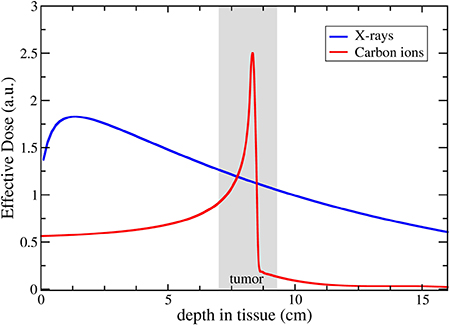

Proton and ion beam therapy has growing potential in dealing with difficult-to-treat tumours, for example, because of the risk of damaging neighbouring sensitive tissues such as the brainstem or visual nerves in the case of head tumour treatments. Also, some treatments may benefit from the use of particles that deliver doses with greater radiobiological effectiveness (RBE) and higher local precision, notably carbon, and in the near future also helium ions.

Recent investigations using ultra-short and ultra-high dose rates (called FLASH) of electron beams showed growth retardation of tumours with the same effect as in conventional therapy, but with minimized impact to the surrounding tissue. FLASH with proton and ion beams is expected to offer additional healthy tissue sparing from beam stopping in the tumour—but the research on this topic is still not completed, and the experiments and evaluations are ongoing. Healthy tissue sparing with FLASH would enable a dose increase as well as a significant reduction of treatment time without additional aggravations. These new key findings may influence the accelerator development for particle therapy considerably in the next future.